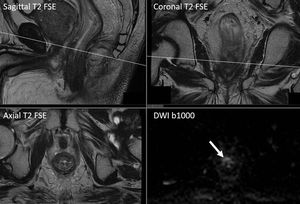

Multiparametric MR Imaging of the rectum for the evaluation of treatment response. DWI is great for pathology detection, and residual disease can be easily highlighted. Images courtesy of Christos Tsiotsios.